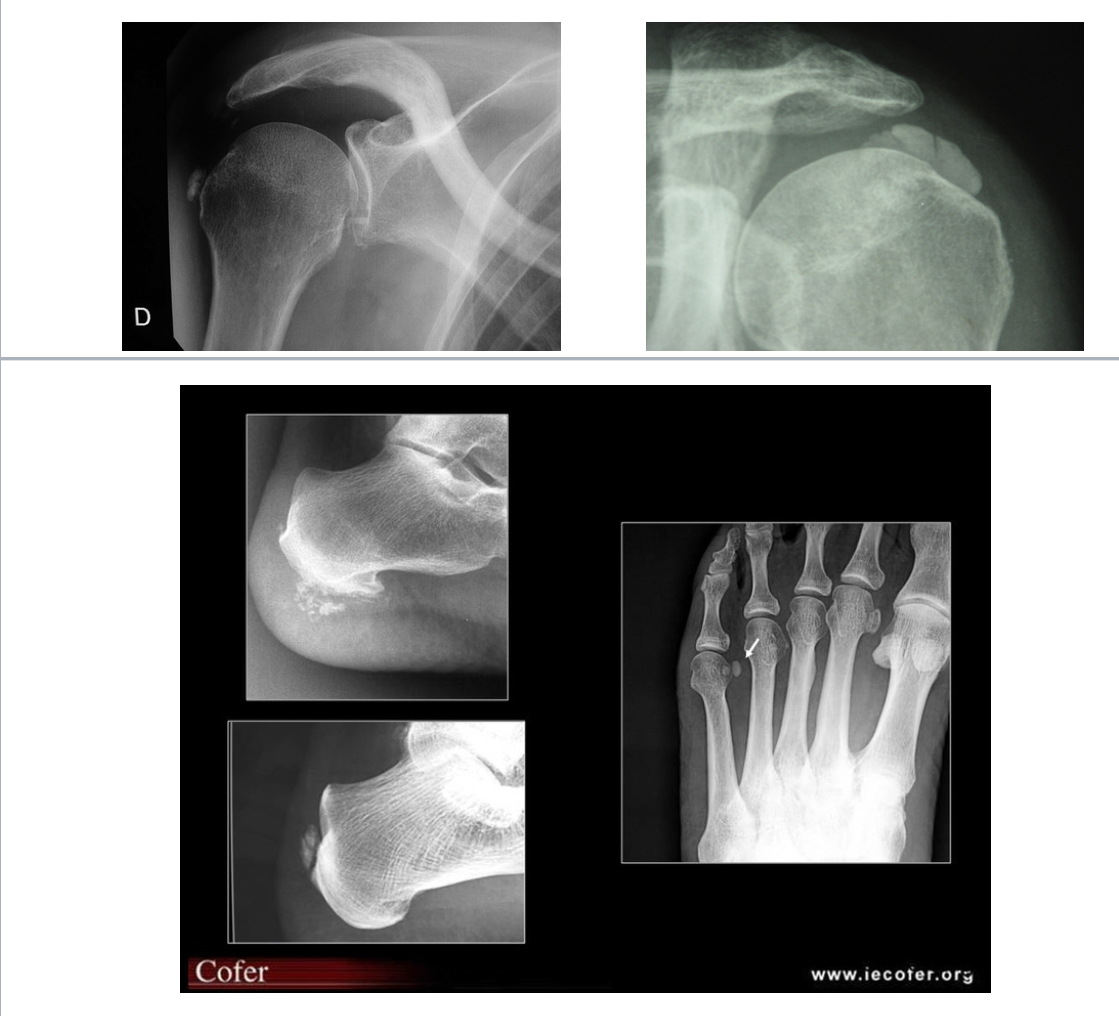

RHUMATISME APATITIQUE

= dépôt dans les structures péri-articulaires (tendons, capsules articulaires et bourses séreuses) de cristaux apatites, généralement épaule, hanche, main, doigts/poignets

Radio :

Opacité calcique arrondie, homogène, sans corticale

Goutte chronique

pincement global +condensation 1ere MTP

Érosions

Infiltration des parties molles

pincement global 1ere MTP

Érosions multiples

Tophus sous-cut

PR

destruction articulaire de la 5e MTP avec érosions multiples